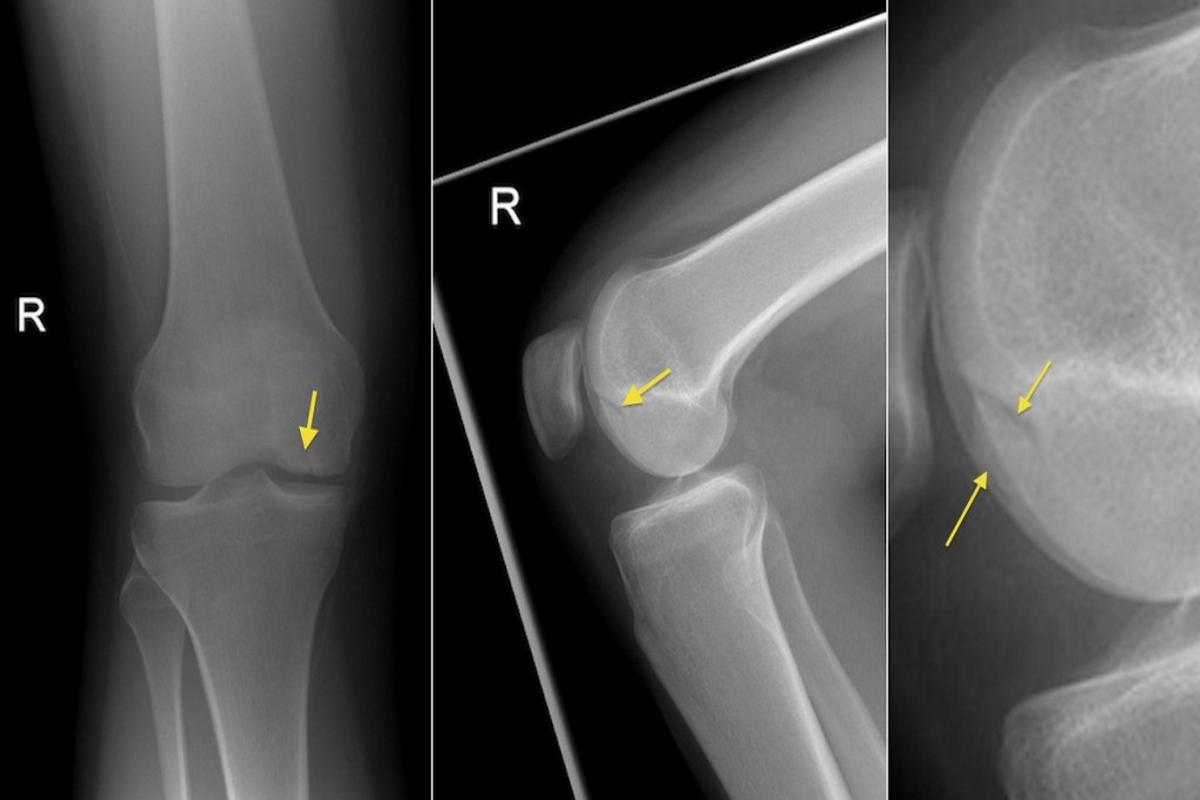

Η διάγνωση βασίζεται αρχικά στην κλινική εξέταση, με εκτίμηση της κινητικότητας, της ευαισθησίας και της σταθερότητας του γόνατος. Ο απεικονιστικός έλεγχος παίζει καθοριστικό ρόλο, με τη μαγνητική τομογραφία (MRI) να αποτελεί τη μέθοδο εκλογής, καθώς απεικονίζει με ακρίβεια το μέγεθος, το βάθος και την εντόπιση της βλάβης.

Σε επιλεγμένες περιπτώσεις, η διαγνωστική αρθροσκόπηση προσφέρει άμεση και αξιόπιστη εκτίμηση της κατάστασης του αρθρικού χόνδρου.